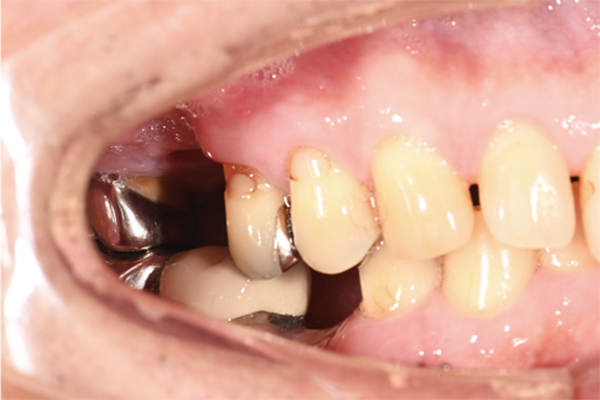

| 主訴 | 奥歯で噛めない、顎が痛い |

|---|---|

| 治療内容 | 奥歯のインプラント治療、前歯・奥歯の被せ物治療 |

| 治療期間 | 6ヶ月 |

| 治療費 | 350万円 |

| 治療リスク | 被せ物をつけた初期の段階で歯がしみることがある(時間とともに改善する) インプラント治療後に3日程度痛みと腫れを伴うことがある |